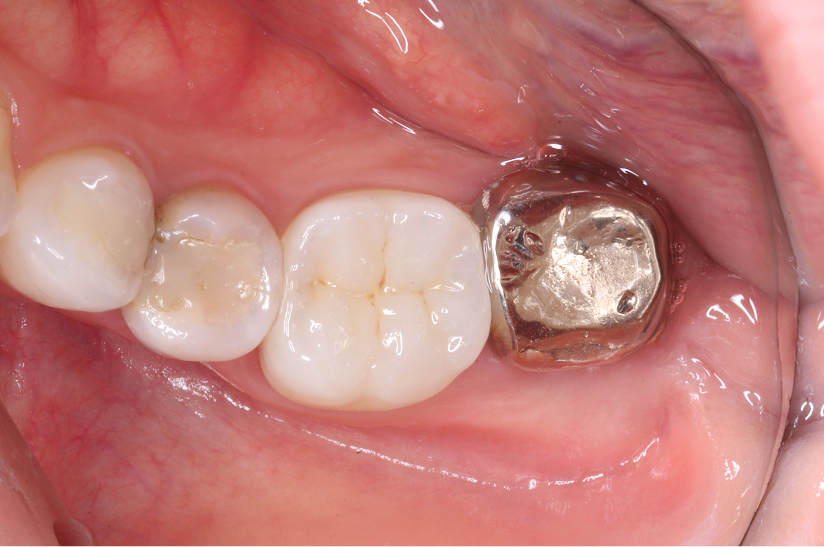

Before

After

主訴

インプラントはできないが、入れ歯もしたくない 。

治療内容

自家歯牙移植 / イニシャルトリートメント(大臼歯)レジンコア

治療期間

3ヶ月

治療費用

550,000

治療の

リスク

術後しばらくしてから骨性癒着、外部吸収を起こす可能性があります。